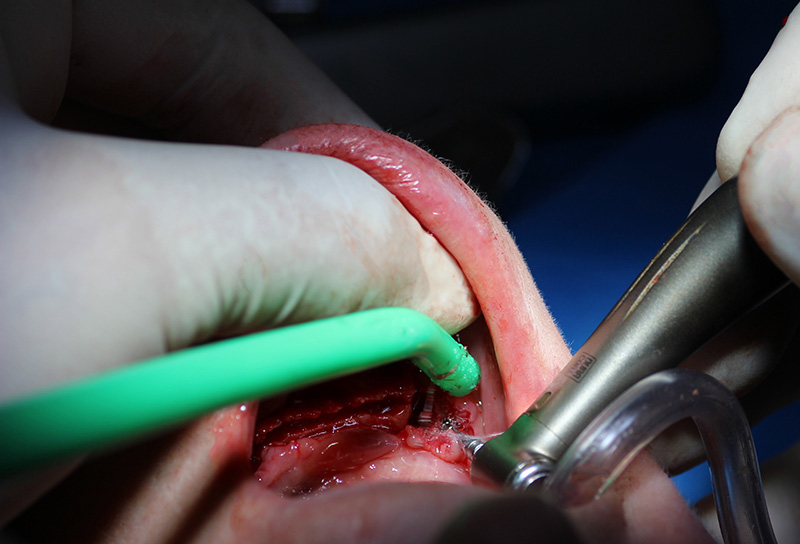

25-ого октября в учебном центре Стом-Лайн был проведен мастер-класс на тему «Одномоментная имплантация с аугментацией (наращиванием) кости, с использованием имплантатов Alfa Gate Dental Implants». Мастер-класс провел главный врач-стоматолог клиники «Нюанс» в Москве Мхитар Казарян.

Мастер-класс начался с обсуждения предстоящей операции и исследования компьютерной томографии, после чего участники смогли присутствовать на операции или следить за ней из учебного центра.